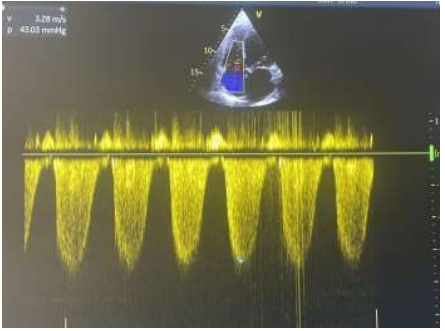

We report the case of a 57-year-old patient, known to have type 2 diabetes for 10 years on oral antidiabetics. The patient was initially admitted to the cardiology intensive care unit for predominantly left-sided congestive heart failure decompensated by a respiratory infection. The clinical examination found a conscious patient, hemodynamically stable, normotensive at 119/65 mmhg, tachycard at 110 beats/min, dyspneic with the presence of jugular vein turgor, edema of the lower limbs, crackling rales mid- fields. the neurological examination revealed a motor deficit in all 4 limbs, 3/5 proximally and 2/5 distally. The electrocardiogram showed a regular sinus rhythm at 105 beats/min, a normal heart axis, QRS at 110 ms, without secondary repolarization disorder. Chest x-ray revealed cardiomegaly, bilateral interstitial syndrome, and right basithoracic focus. A transthoracic echocardiography showed a dilated left ventricle, with an end-diastolic diameter of (58mm, indexed at 37mm/m2) (figure 1), global hypokinesia, severe left ventricular systolic dysfunction, with an ejection fraction of the left ventricle at 30%, moderate mitral regurgitation, left atrial dilatation, pulmonary arterial hypertension at 43 mmhg (figure 2), dilated lower vena cava not very compliant.

Figure 2: Pulmonary arterial hypertension at 43 mmhg